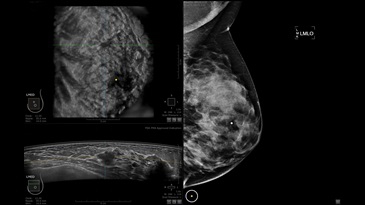

УЗИ-аппарат

GE INVENIA ABUS 2.0

GE INVENIA ABUS – это современный УЗИ аппарат, который создан для точной и эффективной диагностики сканирования с высокой плотностью молочных желез. Выявляемость патологий раковых и предраковых стадий заболевания составляет 55%, что в конечном счете позволяет ставить врачу точные и своевременные диагнозы. Традиционные методы использования маммографии не показывают такой выявляемости, ограничиваясь лишь 3-38%.

УЗИ-аппарат GE INVENIA ABUS позволяет проводить максимально операторонезависимые процедуры, что значительно снижает риск неправильной постановки диагноза и сопутствующие издержки на обработку информации. Система готовит отчет в течение 3-х минут после сканирования, это безусловное преимущество по сравнению с обычным УЗИ сканером.

• датчик с изогнутой апертурой для качественного исследования

• сканирование одной грудной железы в трех проекциях не более 60 сек.;

• обработка результатов за три минуты.